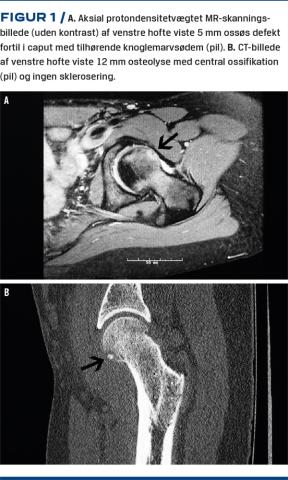

Hun havde bemærket nedsat kraft i venstre ben, men havde ingen natlige smerter. Under den objektive undersøgelse konstaterede man ømhed anterolateralt på låret og en minimal ømhed i lysken. Der var nedsat indadrotation i hoften, men ellers en normal bevægelighed. Der var svagt positivt resultat af en fleksion, adduktion og indadrotationstest og negativt resultat af en fleksion, abduktion og udadrotationstest. Røntgenoptagelser af bækkenet viste normale forhold, ud over en let øget center-edge (CE)-vinkel på 39 grader. Patienten blev henvist til en MR-skanning af venstre hofte (Figur 1 A) og columna lumbalis. MR-skanningen af columna lumbalis viste normale forhold.

Patienten blev dernæst udredt med en CT (Figur 1 B).

Pga. manglende sklerosering omkring læsionen blev der ikke rejst mistanke om osteoidt osteom.